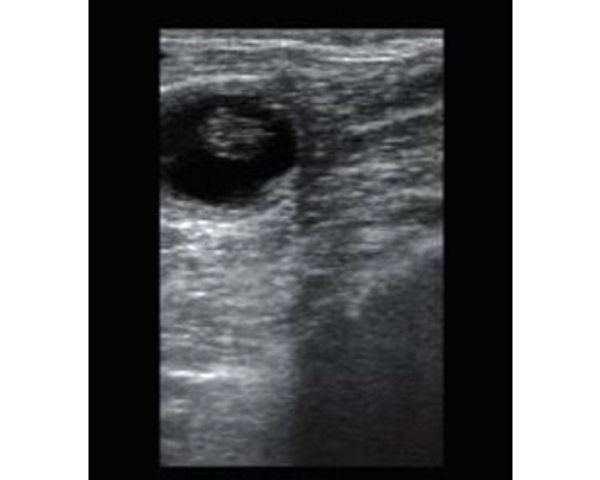

BMV S5 es un ecógrafo ultra portátil y se puede utilizar en diversas condiciones de campo, incluyendo la imagenología reproductiva bovina y equina, así como en la exploración de tendones en equinos.